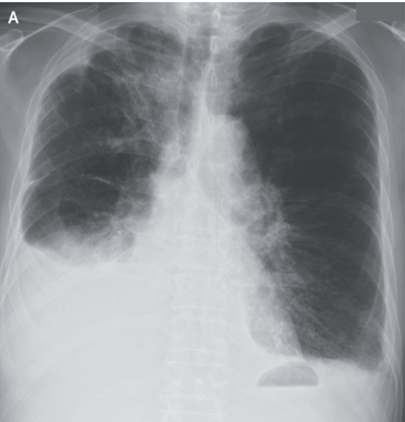

77歳男性。転移性肺腺癌がある。 2週間にわたる呼吸困難を主訴に救急外来を受診。 身体所見としては右肺における呼吸音の減弱が著明だった。 胸部X-pでは右側に胸…